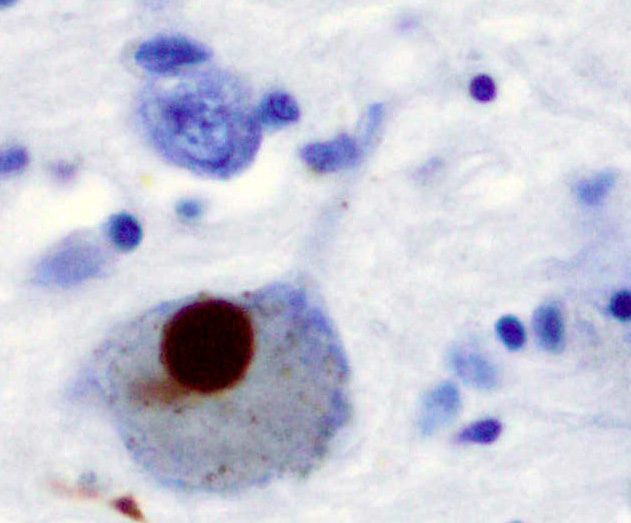

| Positive α-Synuclein staining of a Lewy body in a patient with Parkinson’s disease. | |

The pathological aggregation of alpha-synuclein plays a key role in neurodegenerative disease.[11] The misfolding and aggregation of alpha-synuclein form toxic fibrils, which in turn form pathological inclusions, such as Lewy bodies.[12] These protein deposits are a pathological hallmark of synucleinopathies, and may interrupt crucial neuronal processes, such as functions of synaptic vesicles, leading to neuronal death.[13] Alpha-synuclein is encoded by the SNCA gene, and a mutation in this gene can lead to dysfunctions of the protein structure.[14]